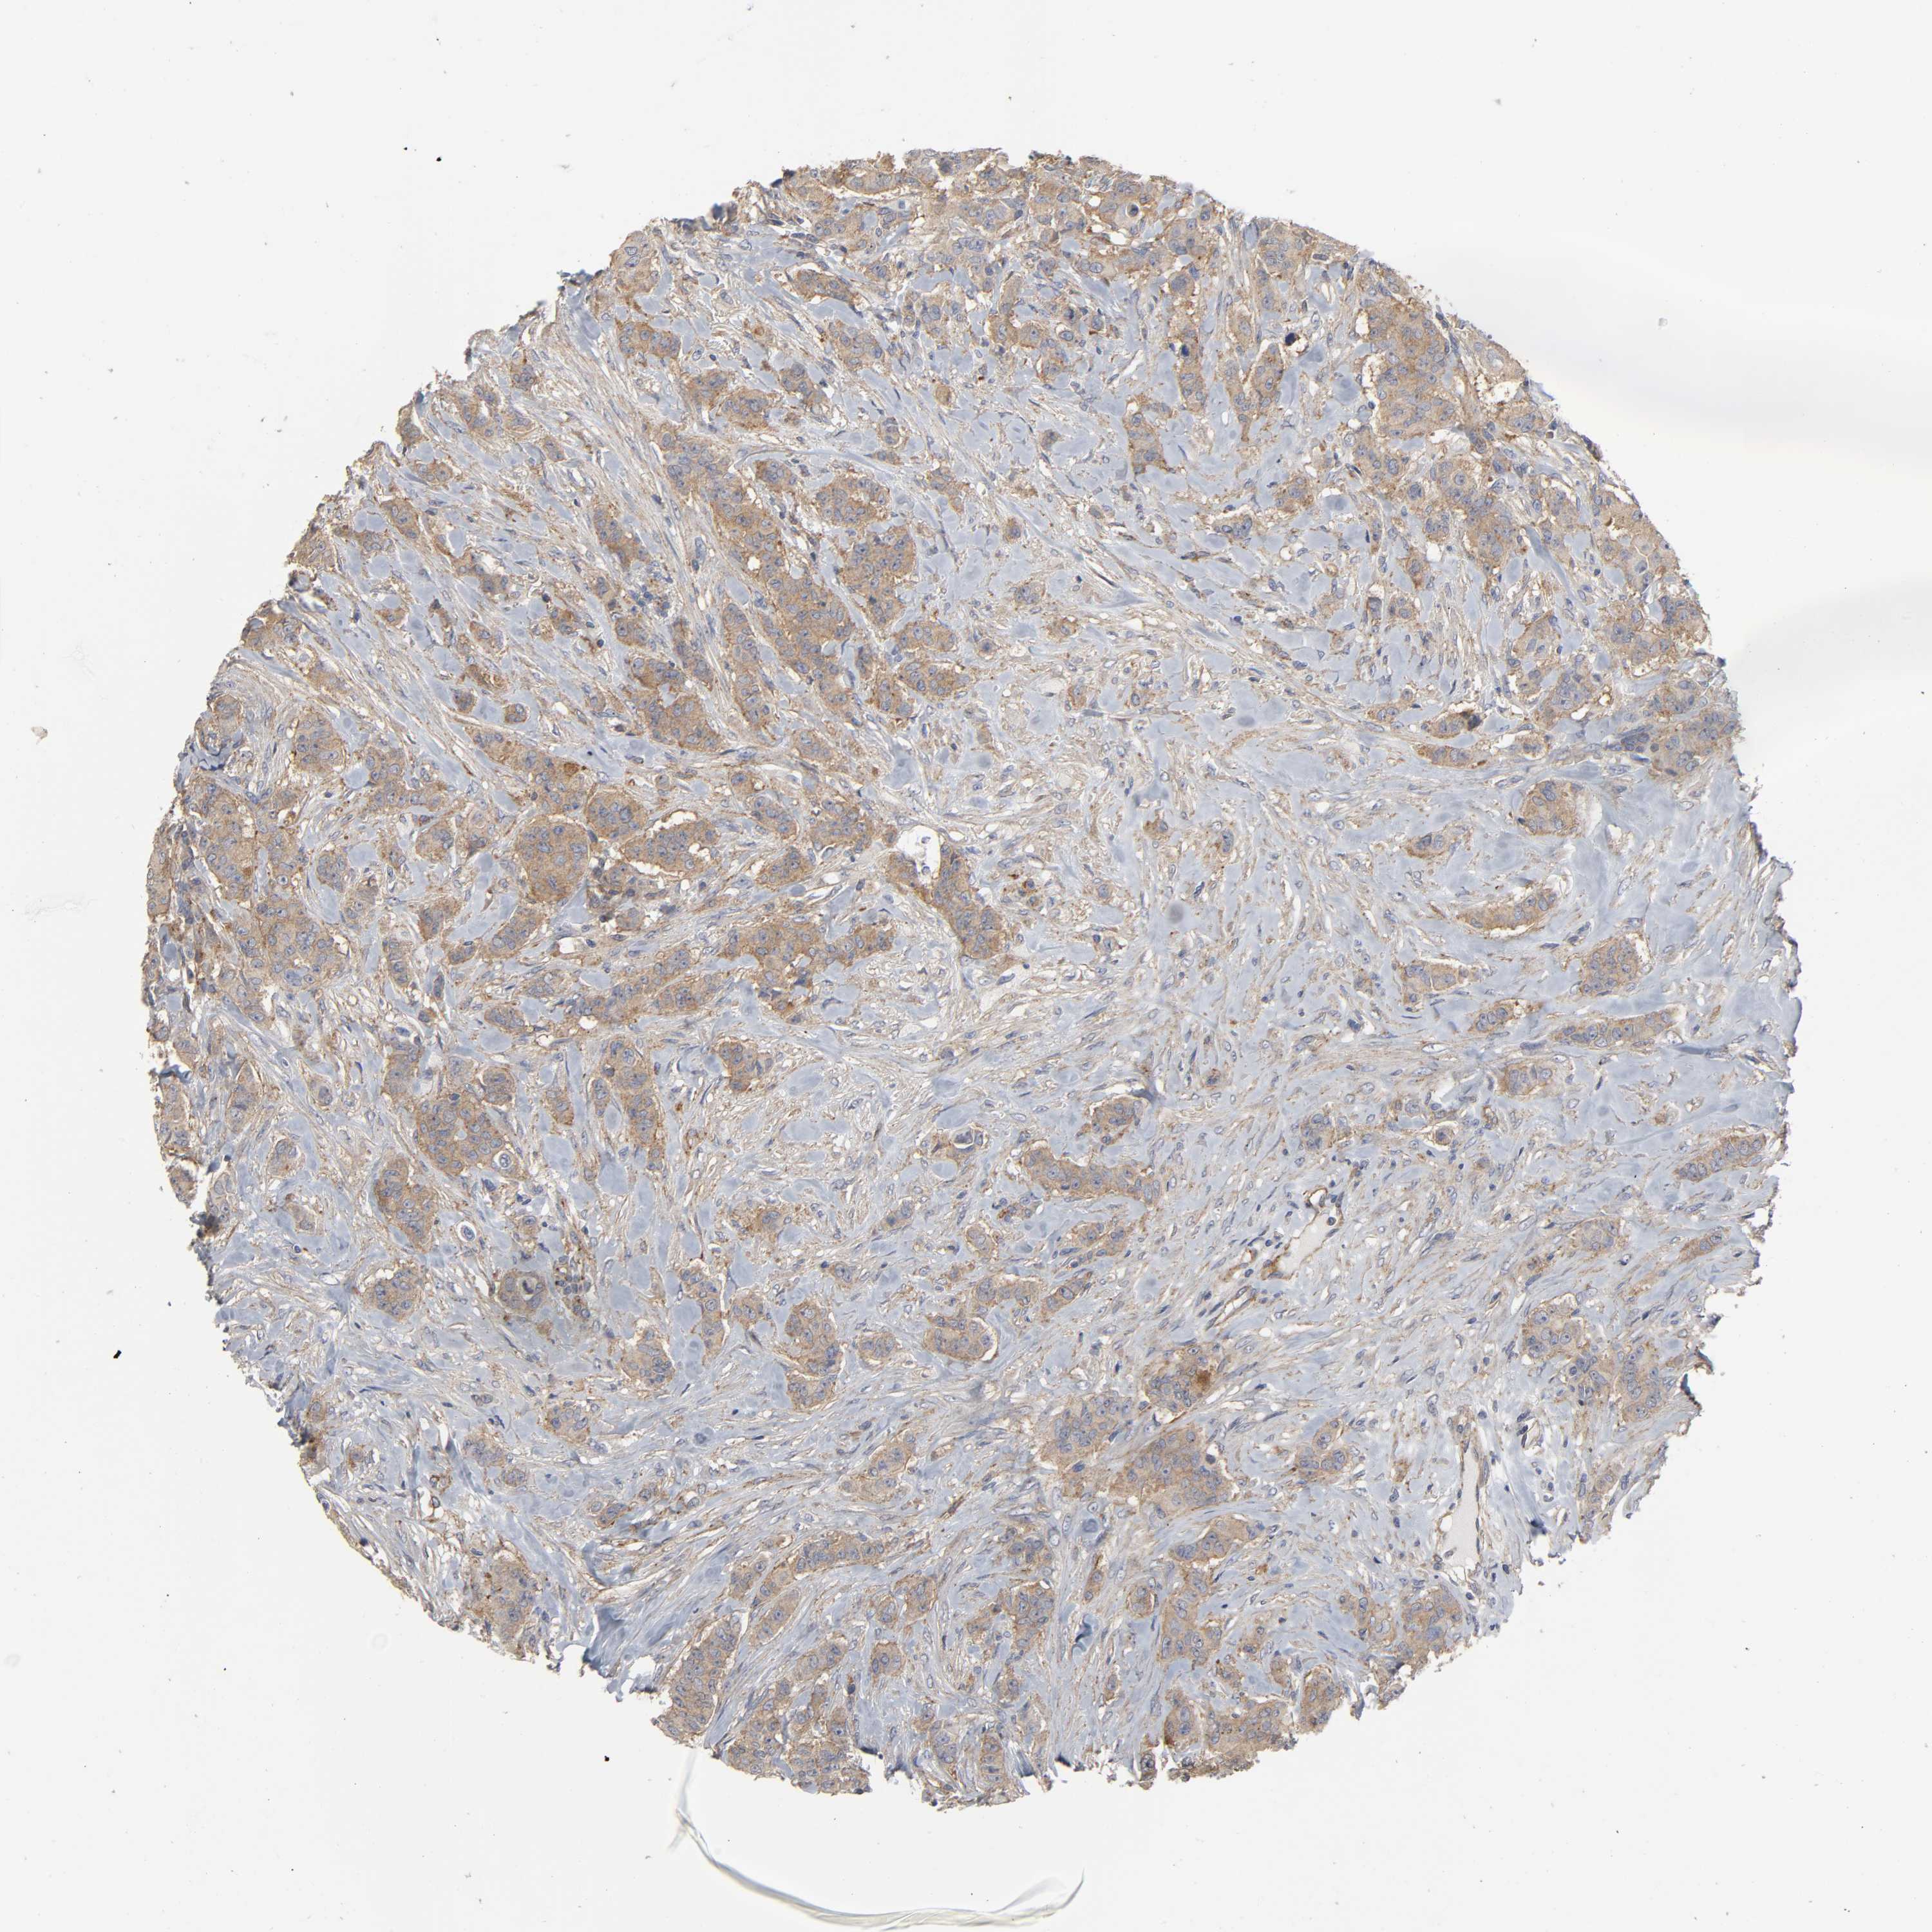

CANCER BREAST CANCER Show tissue menu

BRCA TCGA BRCA VALIDATION PROTEIN EXPRESSION